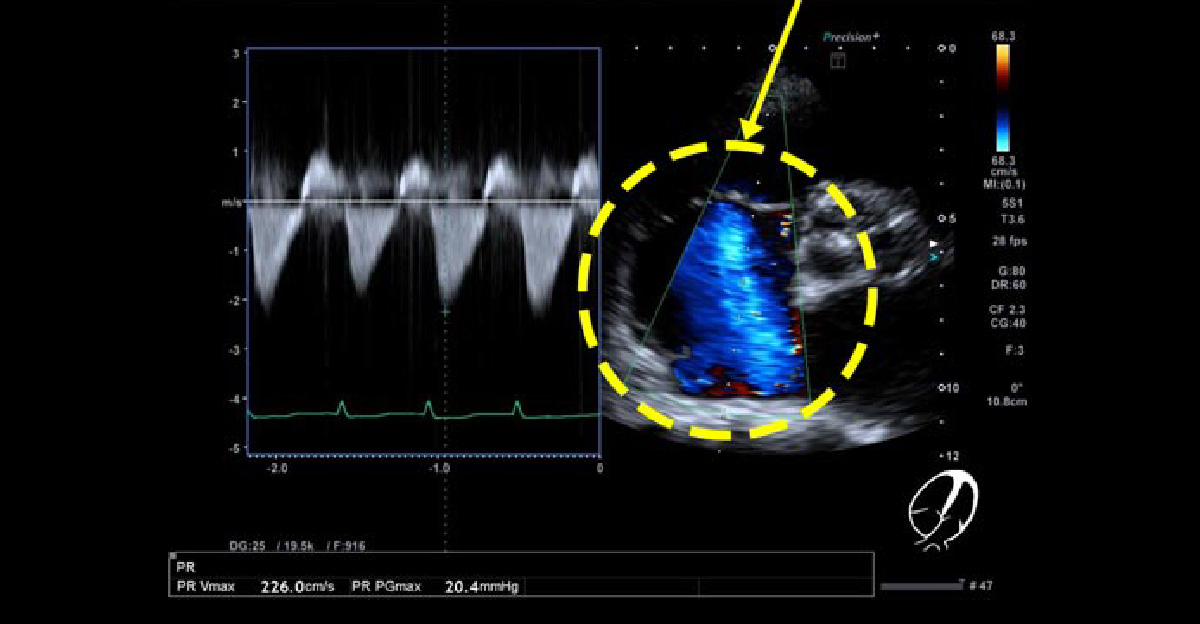

三尖弁閉鎖不全症

慢性心不全の中で、両心不全、右心系拡大が目立つ症例です。三尖弁逆流が高度に認められます。

短軸像で右心房が拡大し、三尖弁逆流ジェットが目立ちます。右下の4腔像でも逆流が顕著です。